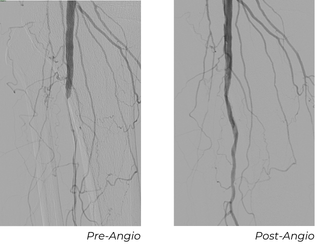

A 77-year-old male presented with a great toe infection requiring amputation. Postoperatively, he exhibited poor bleeding, ischemic wound edges, and delayed healing potential. He had no palpable pedal pulses, known recurrent tibial disease, and several prior interventions. Angiography showed long-segment anterior tibial (AT) and posterior tibial (PT) stenoses and multiple focal occlusions extending distally to the foot.

Using a 6 Fr sheath, a 0.014" Glide Advantage, and a 0.014" CXI, the vessel was predilated with a 2 mm POBA balloon to assist in delivery. A 2.5x80 mm Serranator was then used within the left AT. The posterior tibial (PT) artery was also diseased, but due to limited devices stocked, it was treated with a 2 mm POBA balloon. The result provided restoration of continuous AT flow to the foot and an initial improvement in the PT.

Follow-Up Outcomes

At this patient’s 30-day follow-up appointment, ultrasound showed the AT, which was treated with Serranator, remained fully patent. The PT, treated with POBA, had re-occluded. The wound showed robust granulation tissue and the 2 cm post-amputation cavity had nearly filled, and the ABI was 0.94.

At the 90-day follow-up appointment, ABI remained stable at 1.01, with the AT still patent without restenosis, and the PT remained occluded. The patient’s residual wound had essentially healed with only a small residual eschar.

Key Takeaway

This case illustrates significant durability of the intervention and no vessel recoil after Serration Remodeling Therapy. This enabled wound healing without reintervention through 90 days, contrasted with early PT failure after POBA.

A 68-year-old male patient presented with a second-toe ulcer and a history of multiple prior anterior tibial interventions. For the past 4 years, the patient had a chronic recurrent wound despite multiple successful treatments of his AT with POBA. The last 2 interventions, each failed within a few weeks. Non-invasive testing showed a heavily calcified ABI at 1.7 and a toe pressure of 32 mmHg.

Procedure

A 5 Fr sheath was placed in the below-knee popliteal artery. Selective angiogram of the AT artery again demonstrated the long segment occlusion. Using an 0.018" glide advantage wire and CXI catheter we were able to select the AT. Once the occlusion was traversed, the wire was exchanged for an .014” Roadrunner wire. We performed predilation of the occlusion with a 1.5x40 mm POBA followed by 2.5x100 mm POBA. Next, we performed Serration Remodeling Therapy with the 3.0x80 mm Serranator. Completion angiogram demonstrated complete resolution of the occlusion and excellent flow into the foot.

Before his 30-day follow-up appointment, the patient had undergone a previously planned first toe amputation for osteomyelitis. At 30-day follow-up appointment for the amputation, the patient still had a calcified ABI at 1.6, but the toe pressure increased to 101 mmHg. The post-amputation wound showed substantial improvement as well. At the 60-day follow-up appointment, his ABI was normalized to 1.29, the toe pressure was still maintained at 112 mmHg, and his wound was healed.

This case demonstrates restored vessel compliance, normalization of ABI, and a striking increase in toe pressure following Serration Remodeling Therapy, supporting sustained perfusion and complete wound healing.